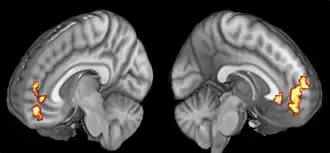

Further research highlighted gratitude's neural correlates, particularly in the medial prefrontal cortex, linking directly to participants' gratitude levels. Comparative studies on happiness interventions ranked gratitude journals highly for their accessibility and impact on happiness. Exploration into the content of journals found entries prompting deeper reflection on gratitude's cause significantly enhanced happiness and well-being. The debate continues regarding optimal frequency of gratitude journaling for maintaining its psychological benefits, with some evidence favoring weekly over daily journaling. Most studies concurred that 3-10 items per journal entry strikes the best balance between fostering gratitude, and avoiding potential boredom.